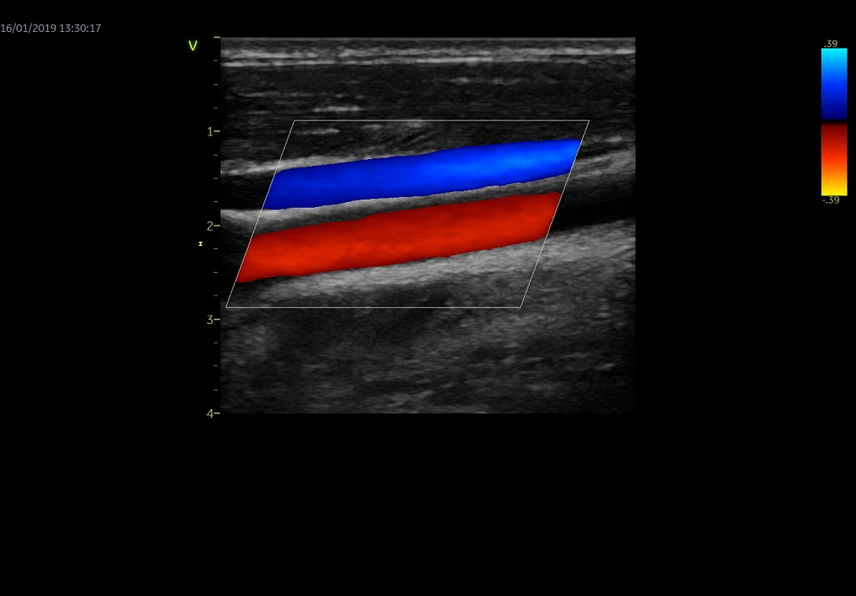

Auto IMT

Обеспечивает автоматическое определение границ и толщины комплекса интима-медиа и выполнение требуемых измерений.